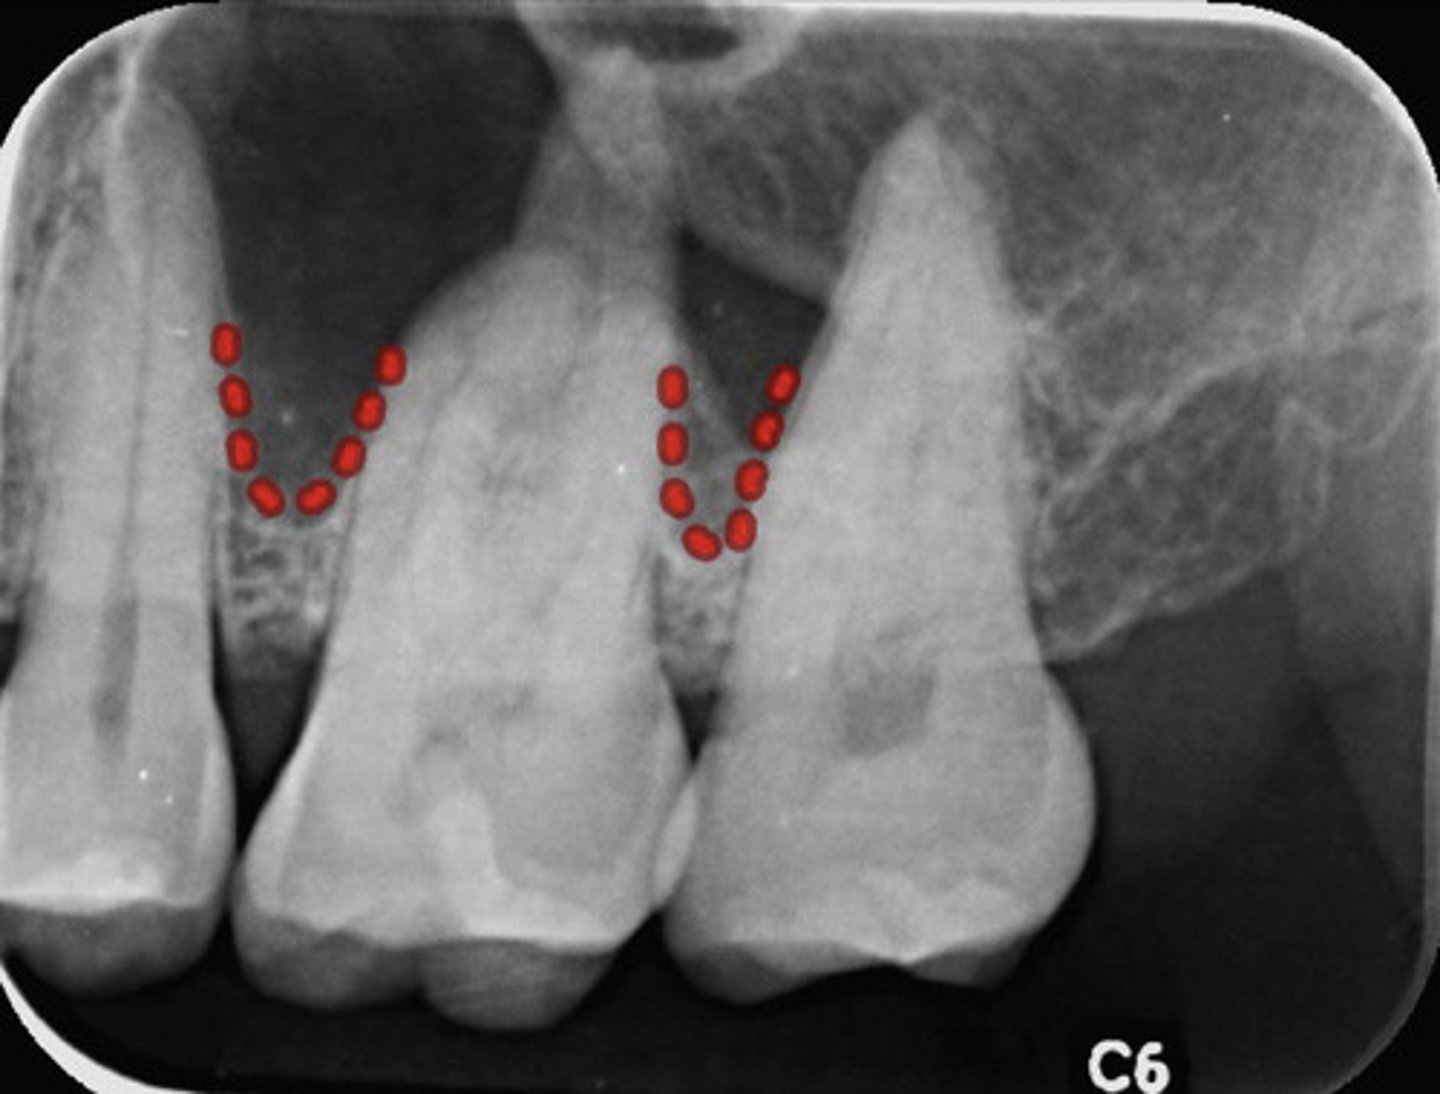

What are the red dots representing?

Dental follicle space